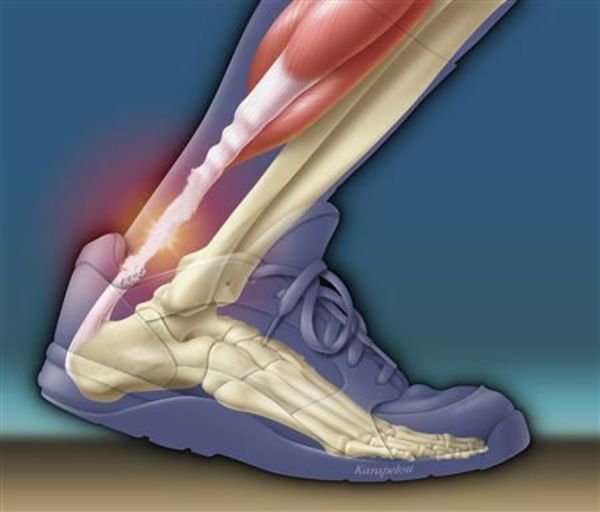

Fluoroquinolonas: actualización sobre reacciones adversas incapacitantes

27 julio 2016

Fuerte advertencia de la FDA sobre efectos colaterales de las quinolonas orales e inyectables FDA, 26 de julio de 2016